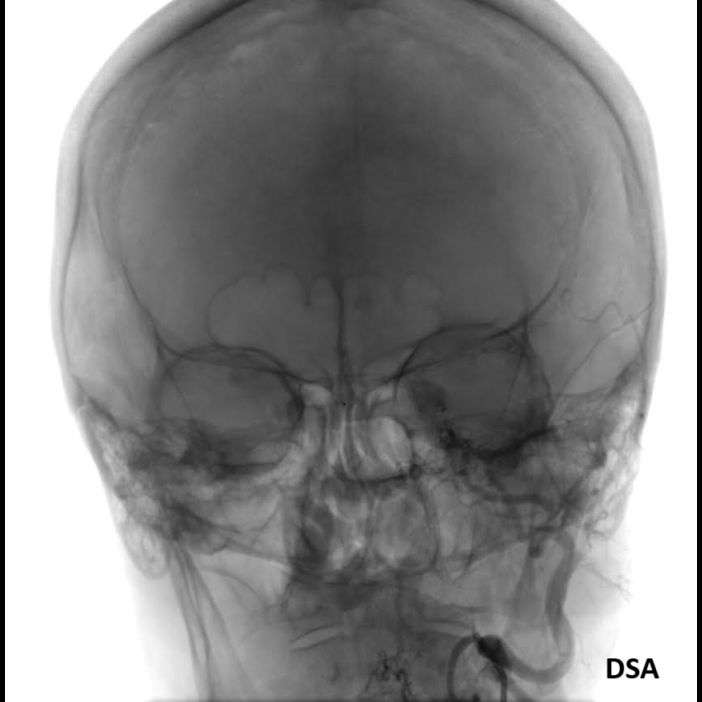

- C) DSA incelemelerinde sol eksternal karotid arter (ok) kateterizasyonunda kontrast maddenin kavernöz sinüse (ok) geçtiği izleniyor. Tedavi sonrası görüntüde kavernöz sinüs ile karotis arteriyel sistem arasında bulunan fistül traktına coil embolizasyon (ok) işlemi uygulandığı görülüyor.

- DSA incelemelerine göre fistüller direkt ve indirekt olarak sınıflandırılmaktadır.

- DSA: Fistülün akış hızını karakterize ederek direkt ve indirekt fistülleri net olarak ayırabilir. ICA defektinin tam anatomik yerini ve ICA veya ECA dural besleyicilerini gösterir. Ayrıca DSA ile endovasküler tedaviler yapılabilmektedir.

- Olgumuzun DSA incelemelerinde sol ICA ve ECA’dan kavernöz sinüse fistülöz bağlantı olduğu izlenmiş ve coil embolizasyon işlemi uygulanarak tedavi edilmiştir.